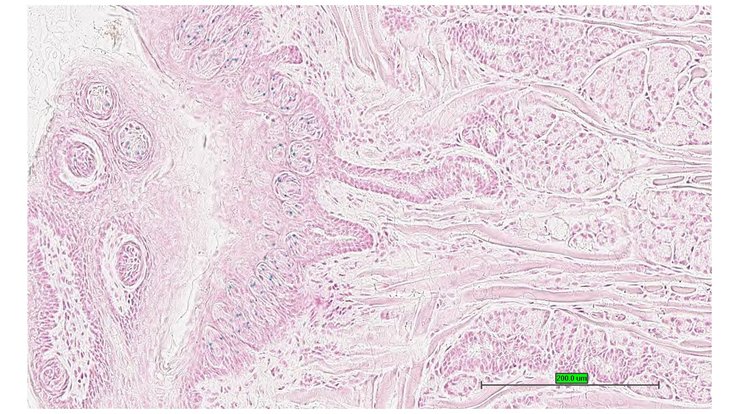

TS28: tongue Present UC Davis_1874954

TS28: tongue Present UC Davis_1874931

TS28: tongue Present UC Davis_1874932